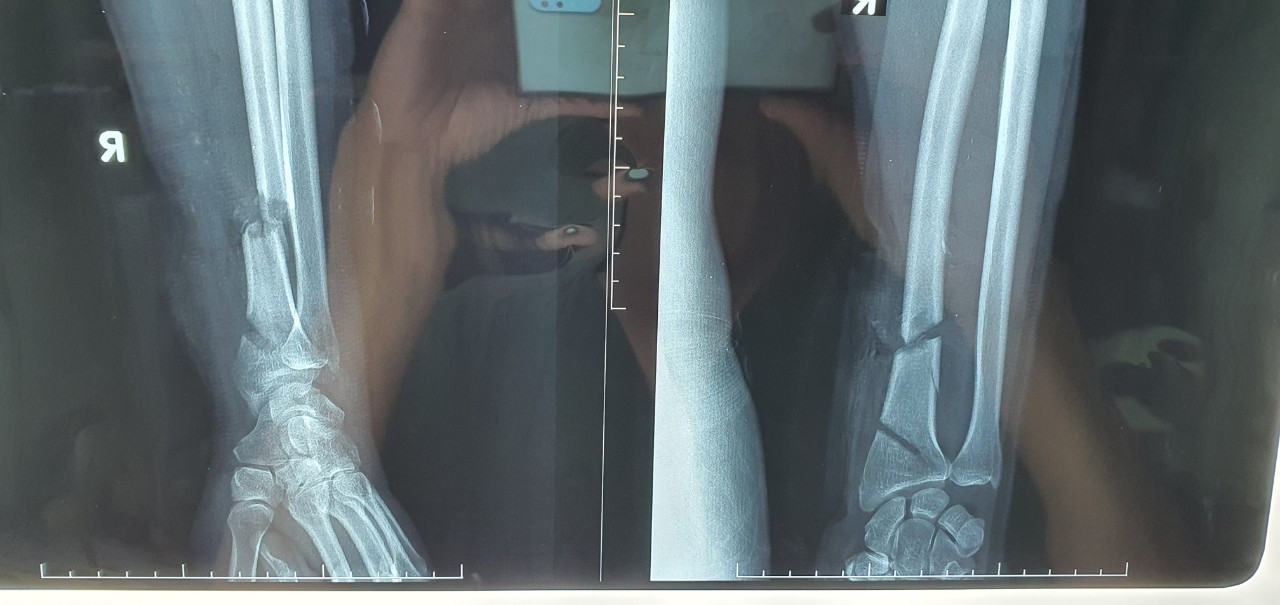

Hình ảnh X Quang xương bị đứt do máy cưa cắt trúng. Các bác sĩ tiếp nhận bệnh nhân và nhanh chóng xử trí cấp cứu. Nhận định đây là trường hợp phức tạp nên đã kích hoạt quy trình báo động đỏ nội viện cần phải phẫu thuật ngay.

Vết thương vùng cổ tay phải 2 đường cắt khoảng 2/3 chu vi cổ tay, đứt gần hết mạch máu, gân cơ và thần kinh. Trong đó, xương quay và một số gân cơ, mạch máu vùng cổ tay đứt 2 đoạn.